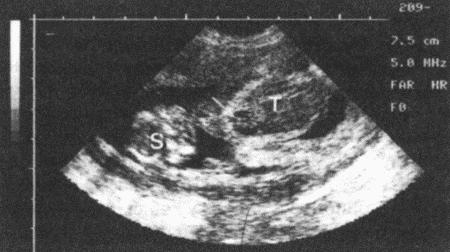

Фиг. 11.5.

Ультразвуковое изображение плода, видны череп (S) и туловище (Т). Ясно визуализируется сердце (указано стрелкой). Датчика 5МГц, шкала в см